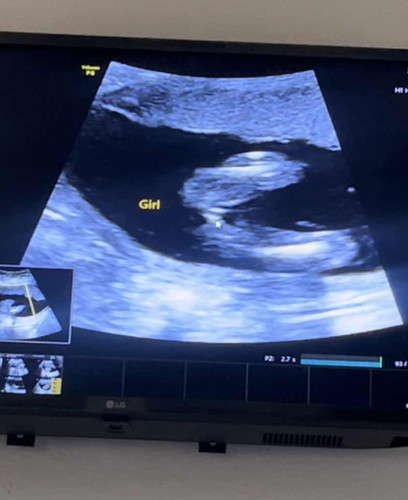

คุณหมอบอกว่าผู้หญิง มีสิทธิ์มีหนอขึ้นมาไหม😅 แม่ๆๆให้ผญ. กี่เปอร์เซ็นต์คะ 🙏 #ขอบคุณสำหรับคำคอมเม้นล่วงหน้าค่ะ #ท้องแรก

บ้านนี้หมอก็ว่าผู้หญิงค่ะ ออกเป็นแฮมเบอร์เกอร์เลย🤣

100%ผู้หญิงค่ะ ภาพเหมือนของเราเลย ชัดเจน